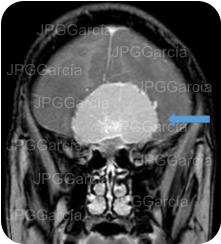

Tumor del plano esfenoidal clasificado por imagen como Meningioma visto a través de resonancia magnética cortes axial y coronal